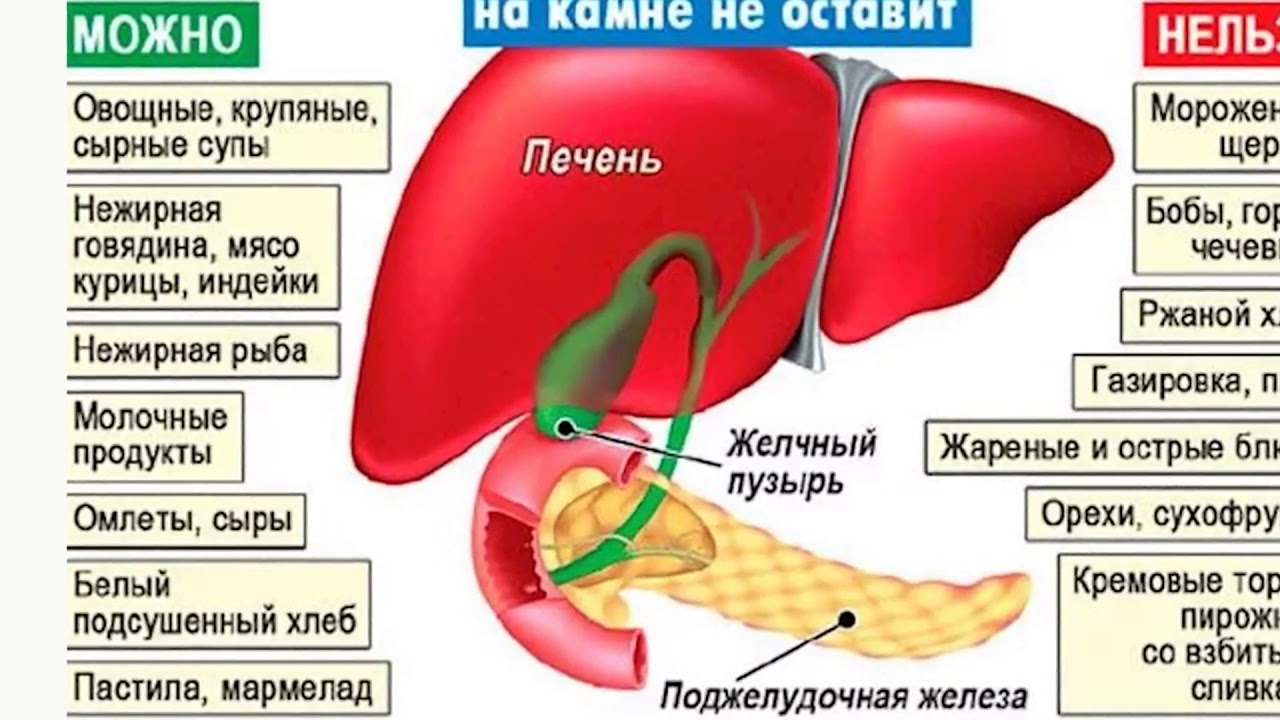

Урегулируйте свой рацион питания, предпочитая низкокалорийную и богатую клетчаткой пищу. Избегайте жирных, обжаренных и пикантных продуктов, а также быстрой пищи.

Употребляйте больше свежих овощей и фруктов, которые богаты антиоксидантами и питательными веществами. Зеленые овощи и ягоды особенно полезны для печени.

Сократите потребление алкоголя до минимума или полностью исключите его из своей жизни. Алкоголь негативно влияет на работу печени и может усугубить ожирение печени.